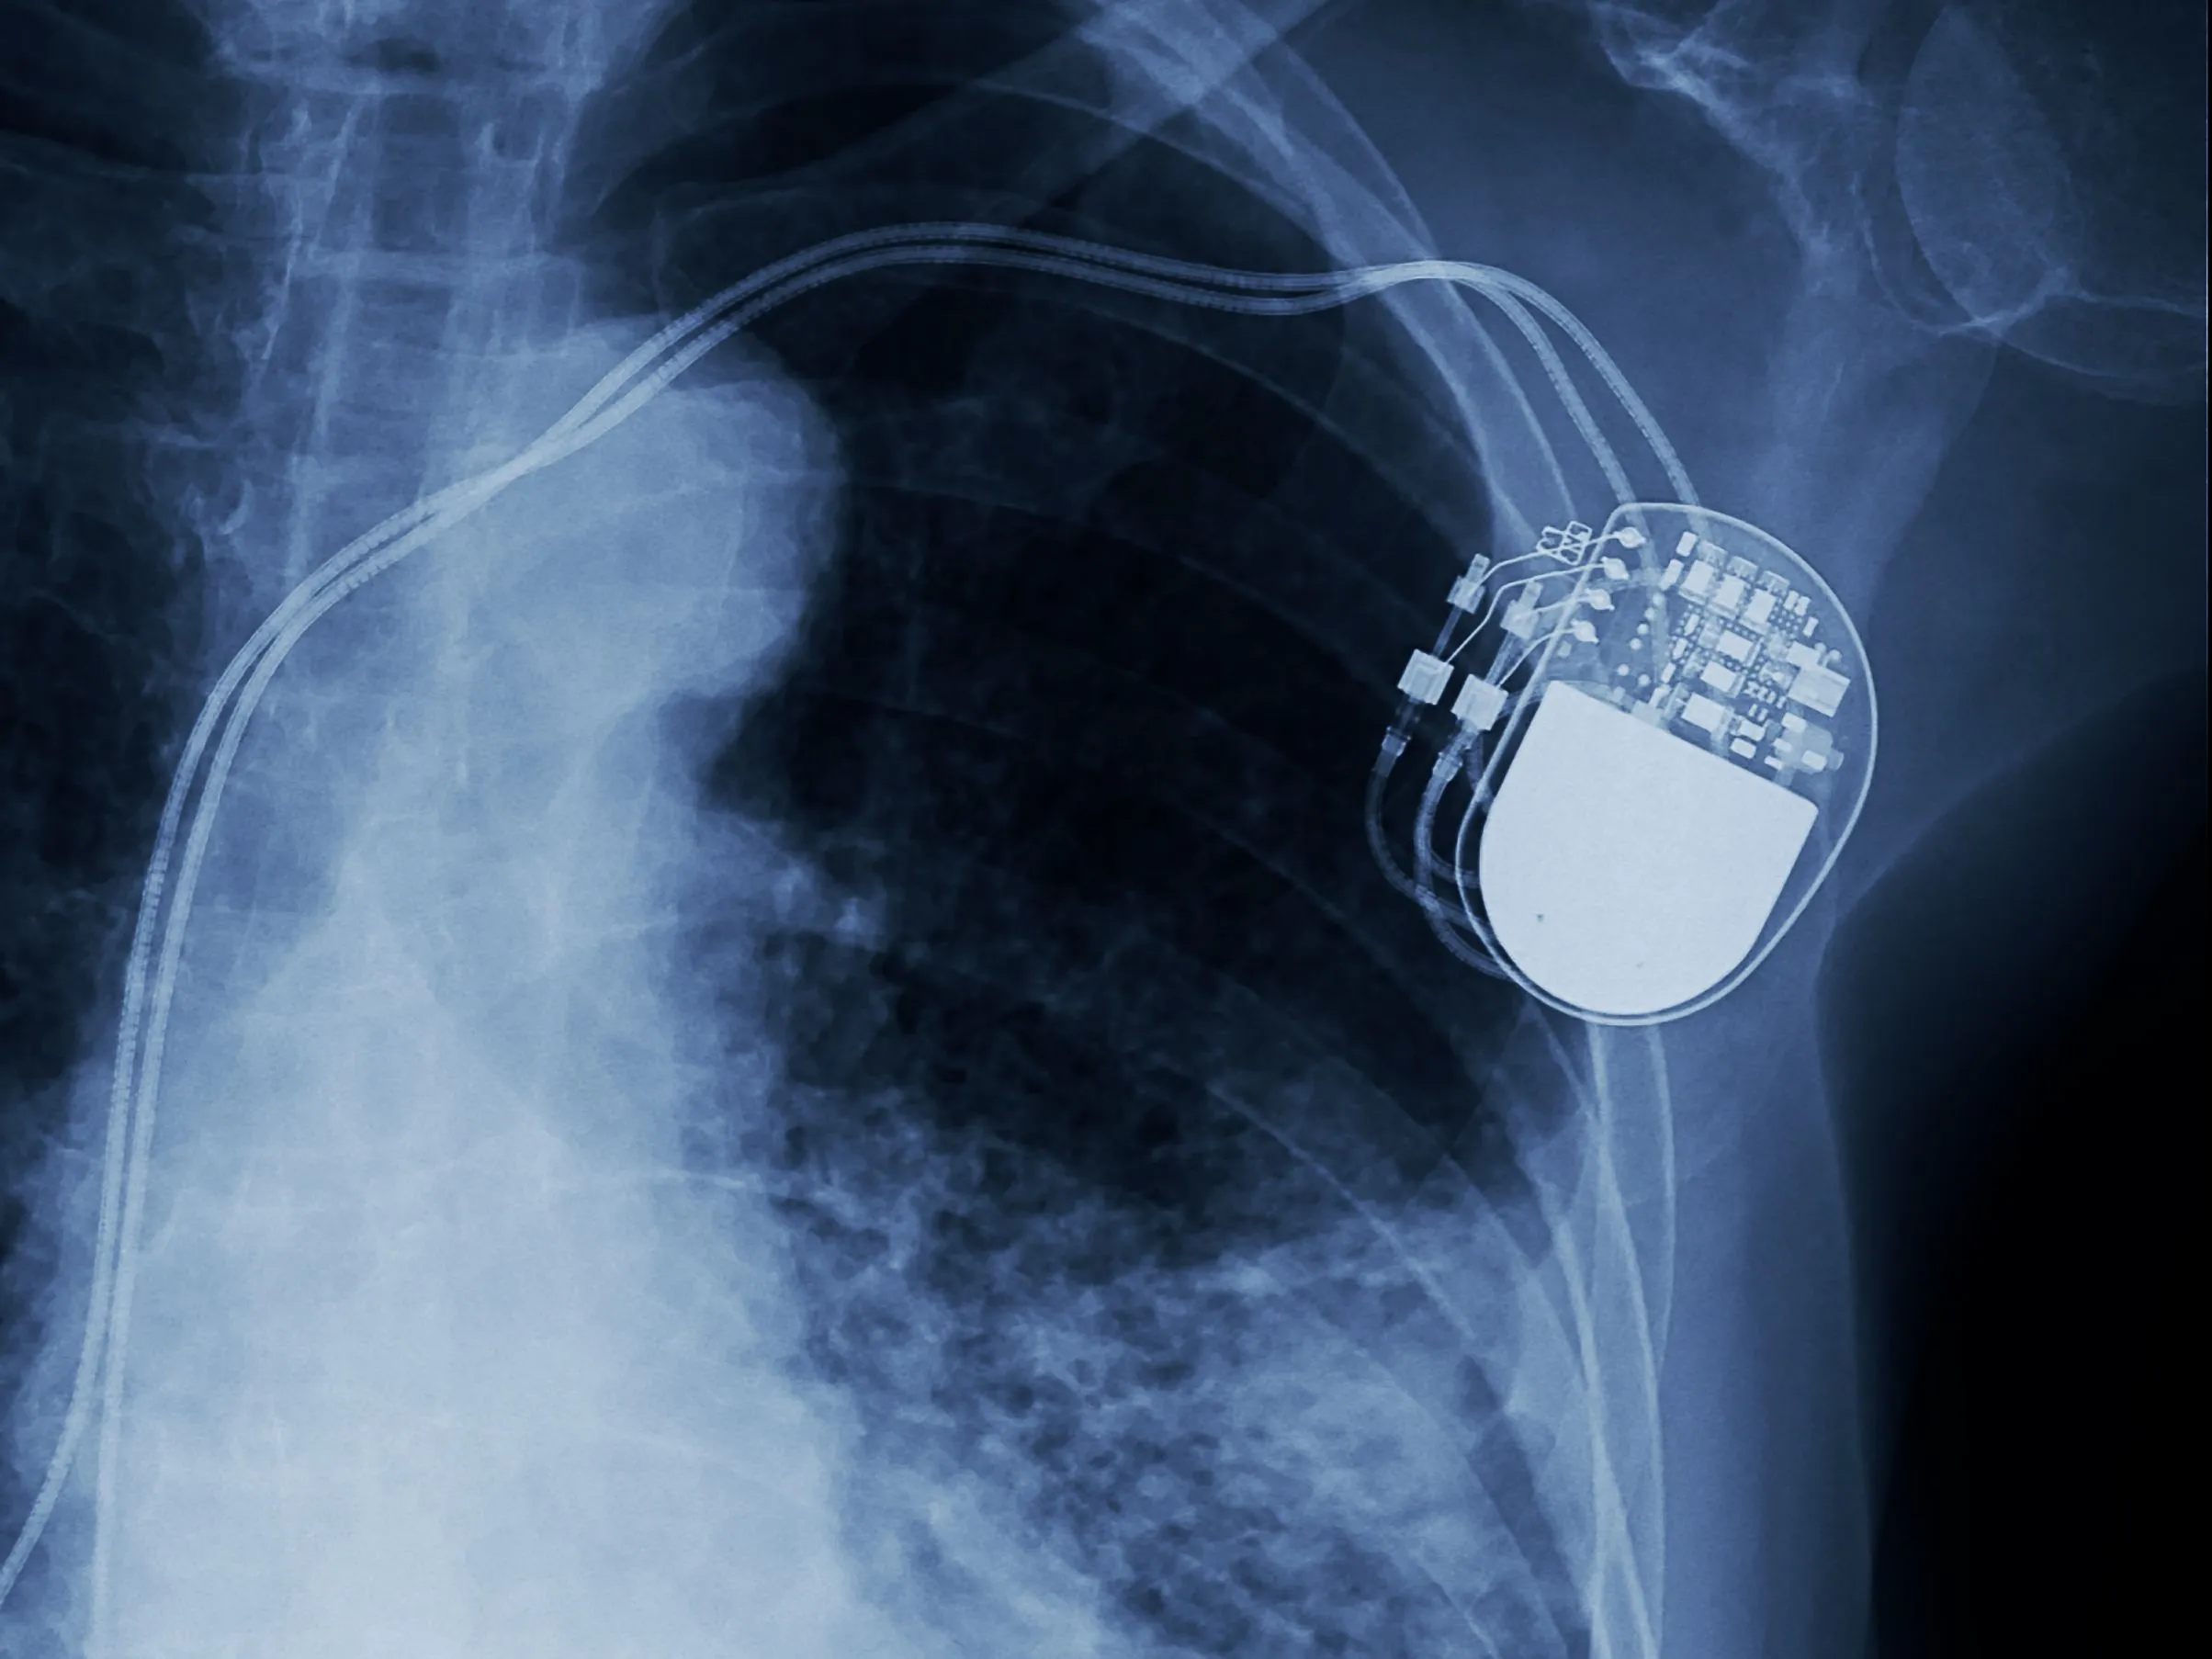

Abbott’s Spinal Cord Stimulator is a low-dose and low-energy pain management device designed to provide pain relief and improve system longevity. It relieves back pain by sending low-level electrical currents directly into the spinal cord. The FDA approved the company’s Proclaim XR recharge-free neurostimulation system for people living with chronic pain.

Abbott’s low-energy spinal cord stimulation is a non-opioid solution offering an innovative approach to chronic pain management. The device works by changing pain signals from the spinal cord to the brain and with low dosages of mild electrical pulses.

This stimulation therapy entails surgically implanting a stimulator that targets the spinal cord to relieve pain in the lower limbs caused by complex regional pain syndrome. Individuals are given a hand-held iPod controller to modify the stimulation settings within certain prescribed limits.